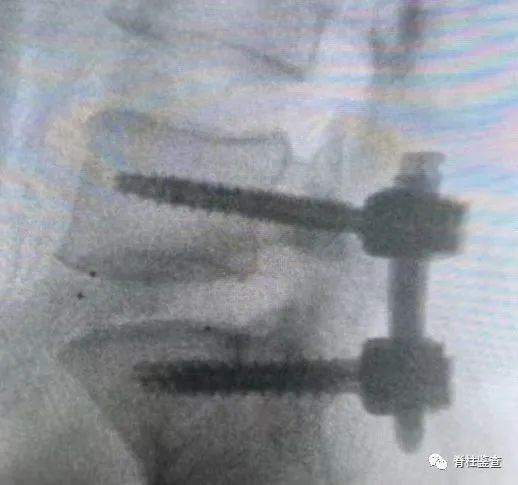

• 置入Cage(椎间融合器)

• 调整Cage位置,确保其作用

• 置入椎弓钉螺钉

• 置入长度及弯度适中的钉棒